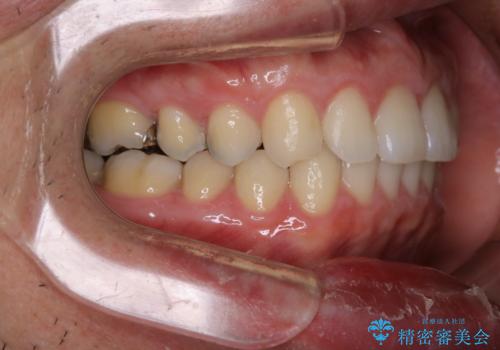

- 全体的に歯と歯の間に隙間があるのが気になるとのことで来院されました。インビザラインでの矯正治療をご希望されました。

隙間については、前歯と奥歯に多数あります。また、上下前歯は、外側に少し倒れているため隙間を閉じつつ、前歯を内側に引っ込めて並べることになりました。